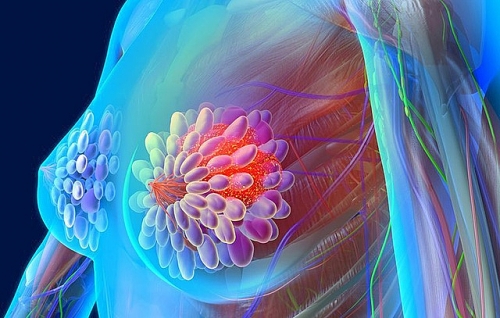

Dấu hiệu nhận biết ung thư vú

Bệnh ung thư vú hiện có tỉ lệ gia tăng trong những năng gần đây. Vậy dấu hiệu nhận biết ung thư vú như thế nào và tại sao phải tầm soát ung thư vú?